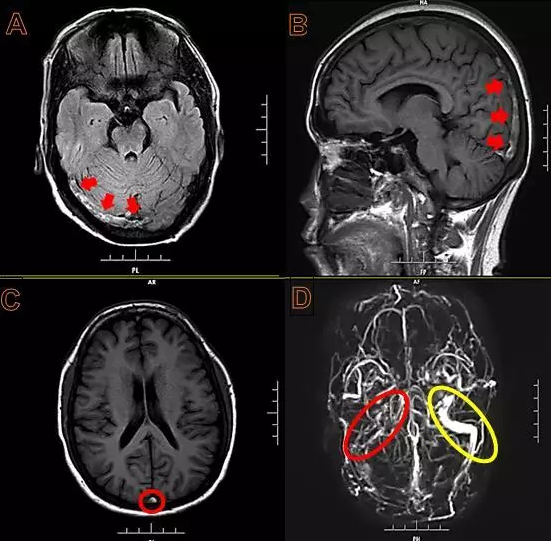

患者上矢状窦下部、窦汇、右侧横窦、乙状窦血栓形成